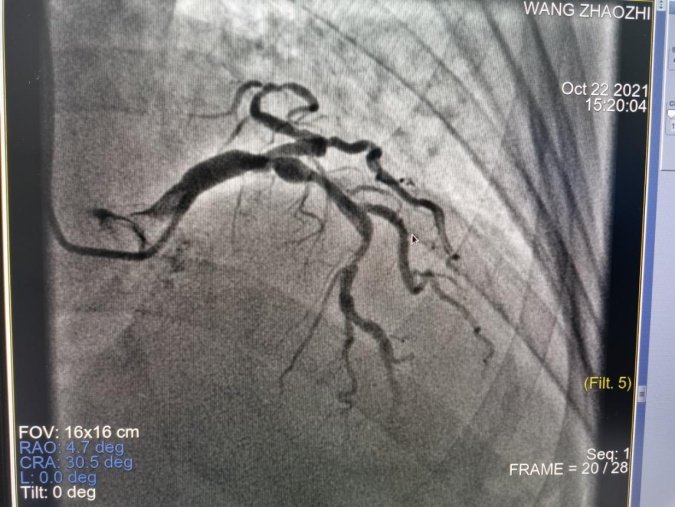

家住绩溪县华阳镇的王×织是今日行心脏冠状动脉造影+心脏支架置入手术的患者之一,他2012年曾行冠脉造影检查确诊冠心病,长期服药,此次因“胸闷、头昏多年加重1周”,经院心内科诊视后,考虑冠状动脉狭窄进展可能,建议住院行心脏造影检查。经过完善的术前准备,10月22日在我院导管室由浙大一附院心内科专家尚云鹏主任主刀为其进行了心脏冠状动脉造影,术中发现冠脉狭窄明显,为其成功实施了心脏支架置入术。手术过程非常顺利,目前该患者术后状况良好。